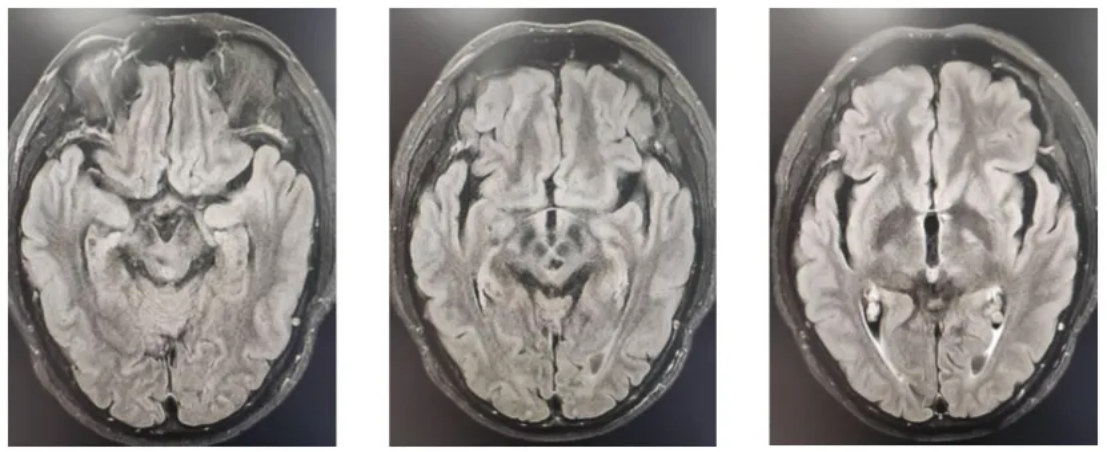

2024-05-19复查颅脑MR:对比2024-01-27 MR(图3):中脑不规则异常信号影,符合DMG治疗后改变,较前变化不大。左侧颞叶海马区、左侧丘脑、侧脑室旁条片状异常信号影,符合DMG表现,范围较前增大,提示肿瘤进展(图4)。

图3 2024-01-27复查影像学

图4 2024-05-19复查影像学